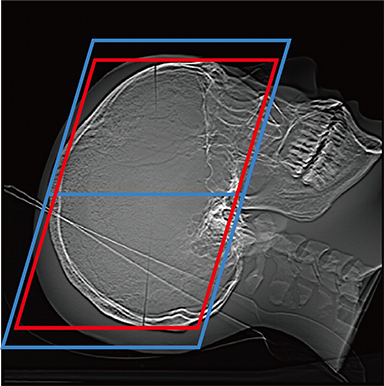

FCT iStream automatically*2 sets the scanning range using the scanogram image by AutoPose function. Since the margins can be set in advance, the range can be customized according to the preference of the facility. iTilt automatically creates and enables observation of tilted images during scanning.

When set to RB Line

Red: automatically set position, Blue: automatically set position + margin setting position